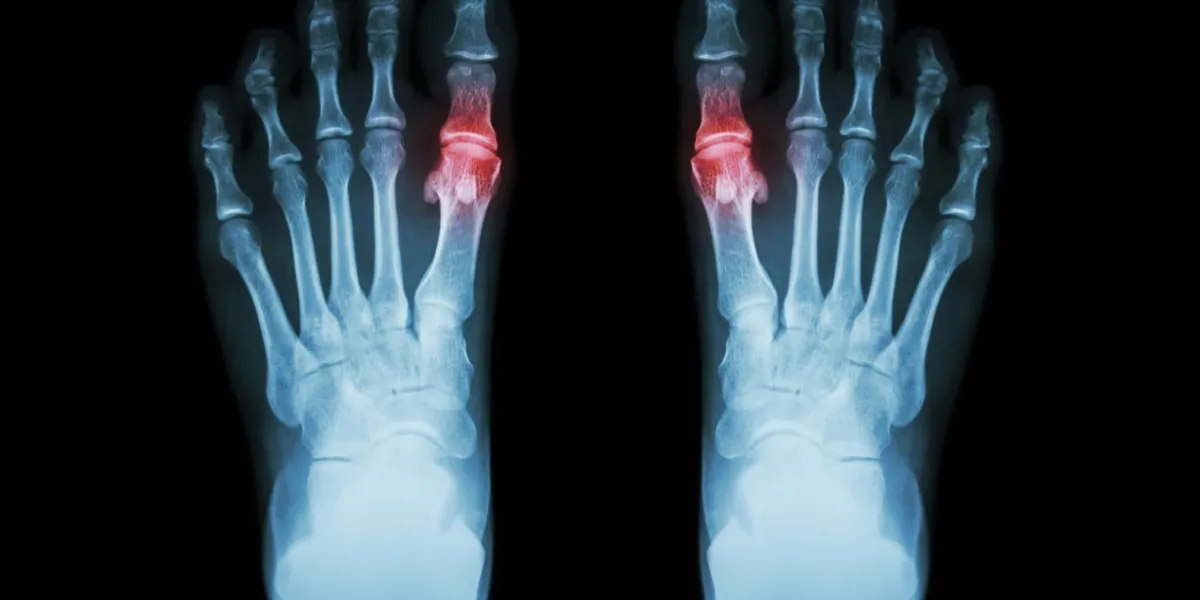

gout , rheumatoid arthritis ( film x-ray both foot and arthritis at first metatarsophalangeal joint ) ( medicine and science background )

Istock

La goutte correspond à une atteinte articulaire inflammatoire, ou arthrite, due à un excès d’acide urique. Elle provoque de violentes douleurs, souvent au niveau du gros orteil. Elle est favorisée par de mauvaises habitudes alimentaires et à tendance à récidiver.